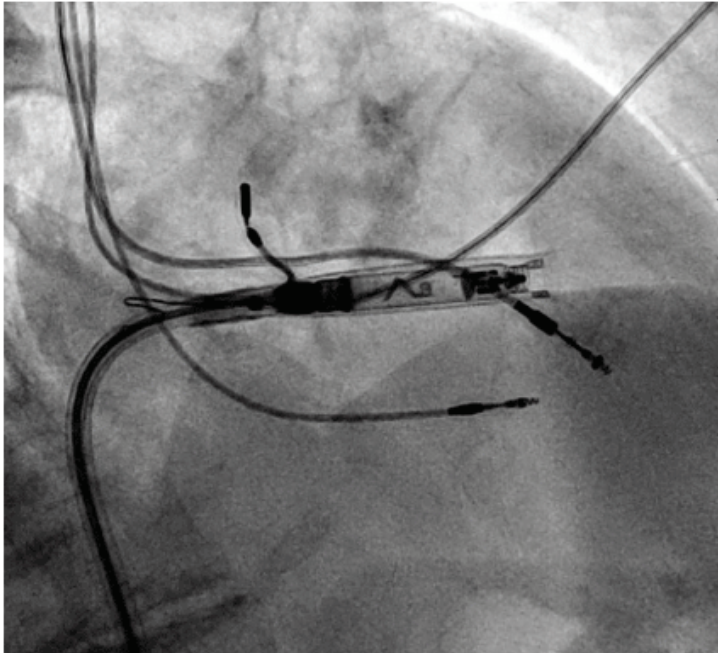

The leadless pacemaker was advanced into the septal myocardium using clockwise rotation of its helix, as confirmed by fluoroscopy. Excellent active injury current was noted, indicating effective myocardial capture, with optimal sensing, impedance, and capture thresholds. The device was released from the catheter (Figure 4), which, along with the introducer sheath, was then removed. Hemostasis was achieved using a figure-of-8 suture and manual pressure. There were no complications and the patient was discharged to home without incident.

A pigtail catheter was advanced through the introducer sheath, and a contrast venogram was performed to identify the base of the right atrial appendage. The AVEIR catheter was advanced through the introducer sheath and navigated to the anterior base of the right atrial appendage (Figure 5). The implantation procedure was similar to that of the RV device description. Atrial capture, sensing, and impedance parameters were excellent. The device was released, and the deployment catheter was removed from the body. Figure-of-8 sutures were again applied to achieve hemostasis. The pacemaker generator was dissected and removed from the pocket and the chronic leads were capped without incident.